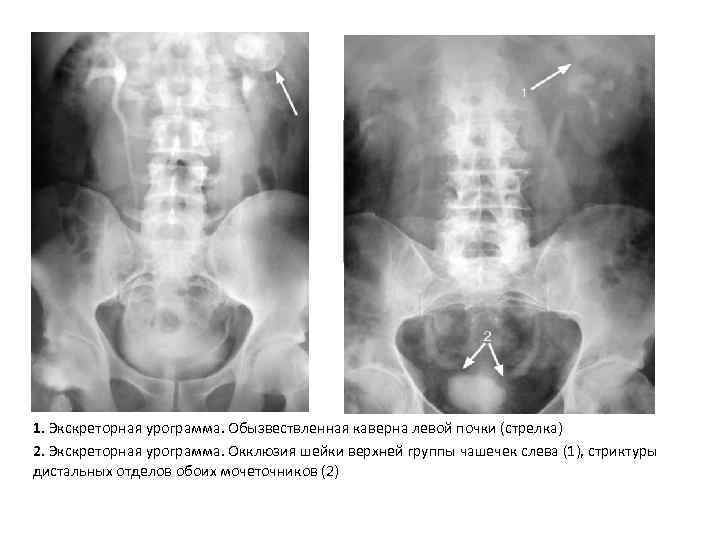

Понимание кавернозного туберкулеза почки

Раздел: Мудрость в деталях